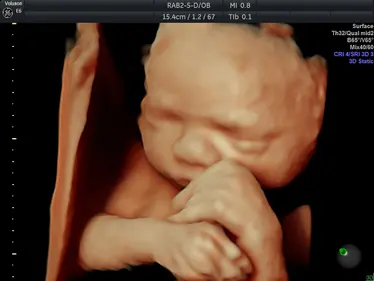

Gallery: 4D Scan Images & Videos

All of the baby scans we perform here at First Encounters are carried out using top-quality ultrasound equipment. For 3D/4D scans, we use the GE Voluson E6, featuring genuine HDLive technology. GE Healthcare are the world’s leading providers of pregnancy scanning equipment, and HD Live scans give an unparalleled level of detail and clarity.

Scroll down to view some examples of the 4D scan images and videos our sonographers are able to capture.

4D Scan Images

During your 3D/4D scan, we’ll capture multiple photographs of your unborn baby, giving you and your family a set of stunning keepsakes that you’ll treasure forever. All of your scan images will be available to download from photocloud™, plus we can provide glossy souvenir photos for you to take home.